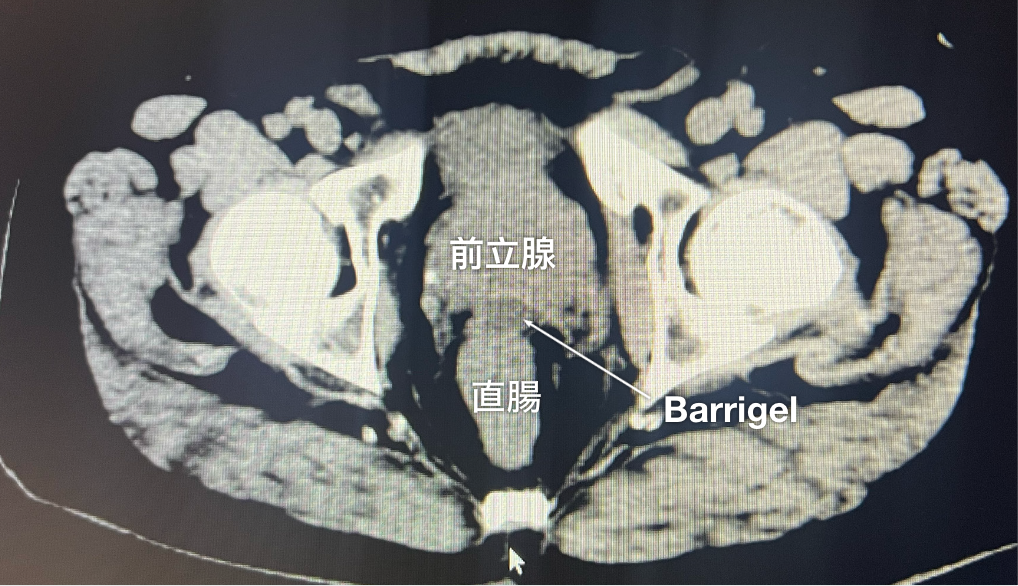

CT画像

CT画像提供:Glen Gejerman, MD

Radiation Oncologist; New Jersey, United States